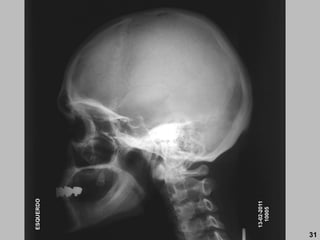

LATERAL (ortostático e decúbito)

RC: 5 cm superior ao MAE (2 polegadas).

DFoFi: 1 metro

Básica